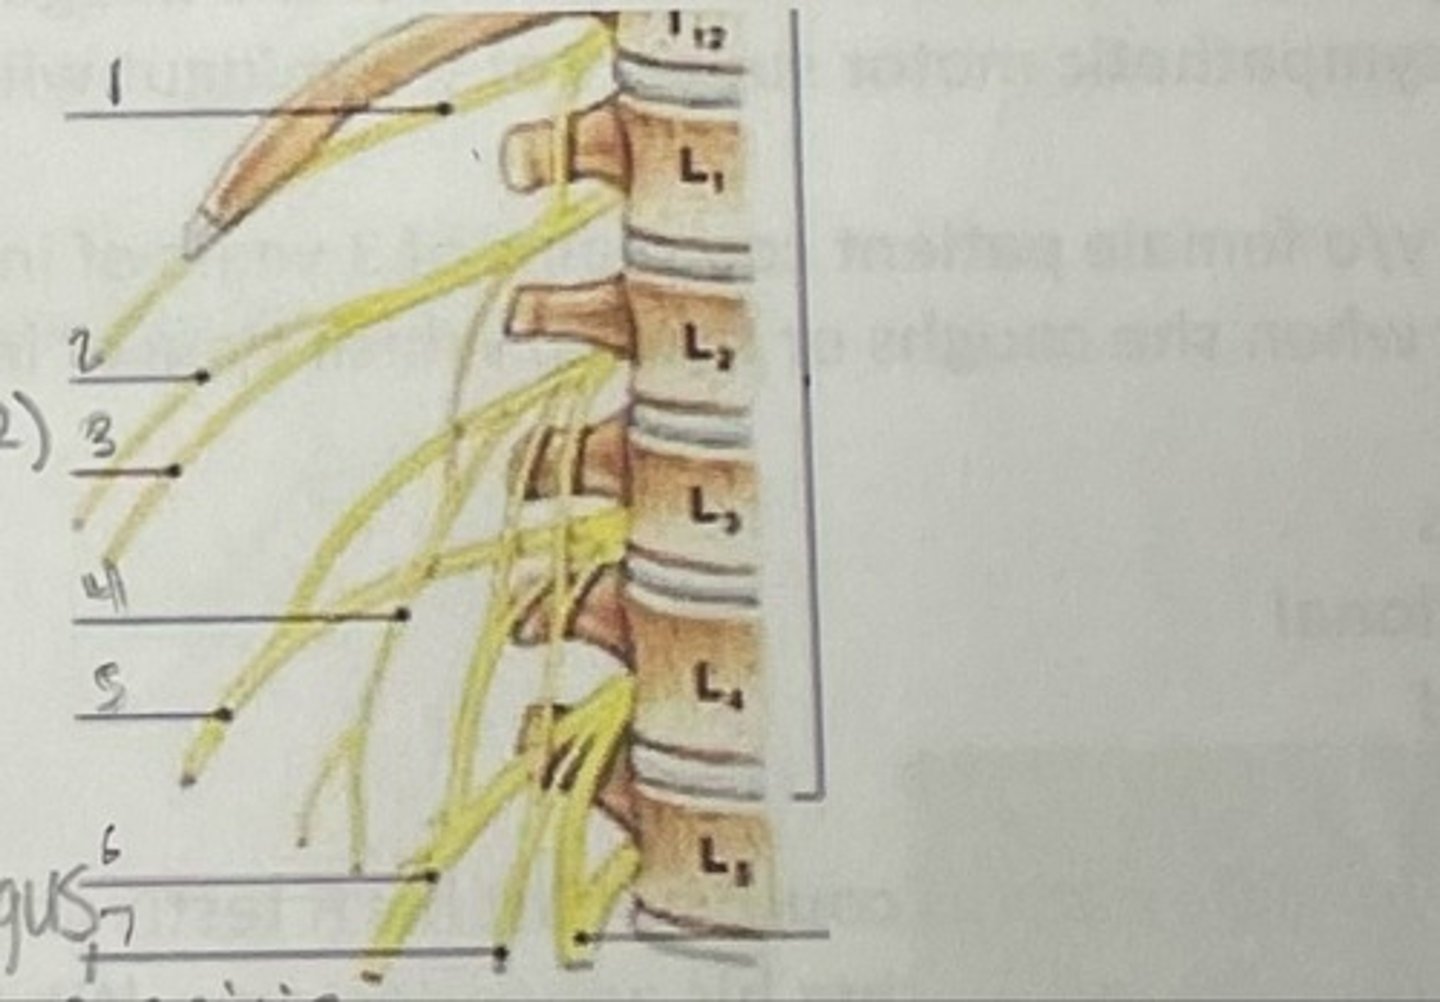

Subcostal nerve (T12)

What is 1

Illiohypogastric nerve (T12/L1)

What is 2

Illioinguinal nerve (L1)

What is 3

Genitofemoral nerve (L1-L2) ; on top of psoas

What is 4

lateral femoral cutaneous nerve (L2-L3)

What is 5

Femoral Nerve (L2-L4)

What is 6

Obturator nerve (L2-L4)

What is 7